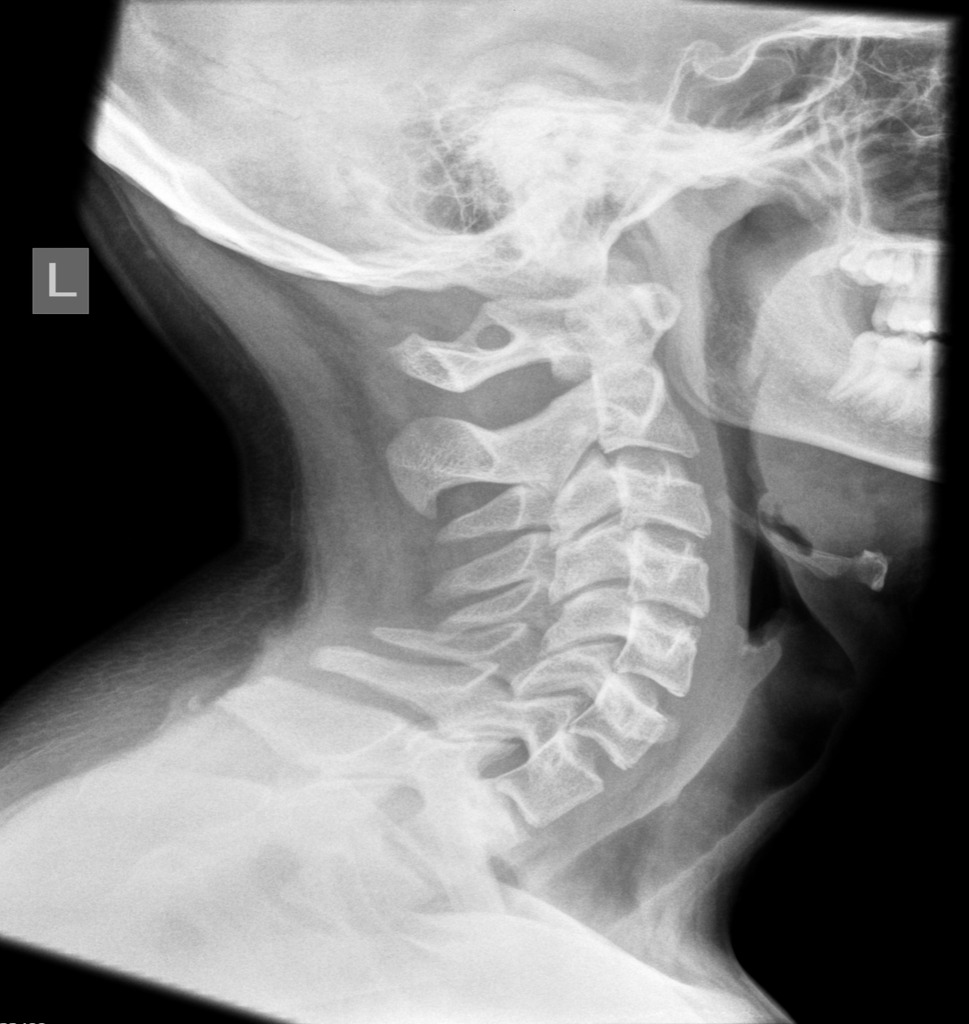

Проведение диагностики

Для постановки диагноза назначается рентгенография черепа и шейного отдела. Аномалия Киммерли чётко видна на рентгенограмме при обследовании краниовертебрального перехода. Если пациент жалуется на ушной шум, чтобы исключить лор-болезнь, требуется консультация отоларинголога. Проводится аудиометрия, при необходимости назначаются дополнительные методы исследования слуха.